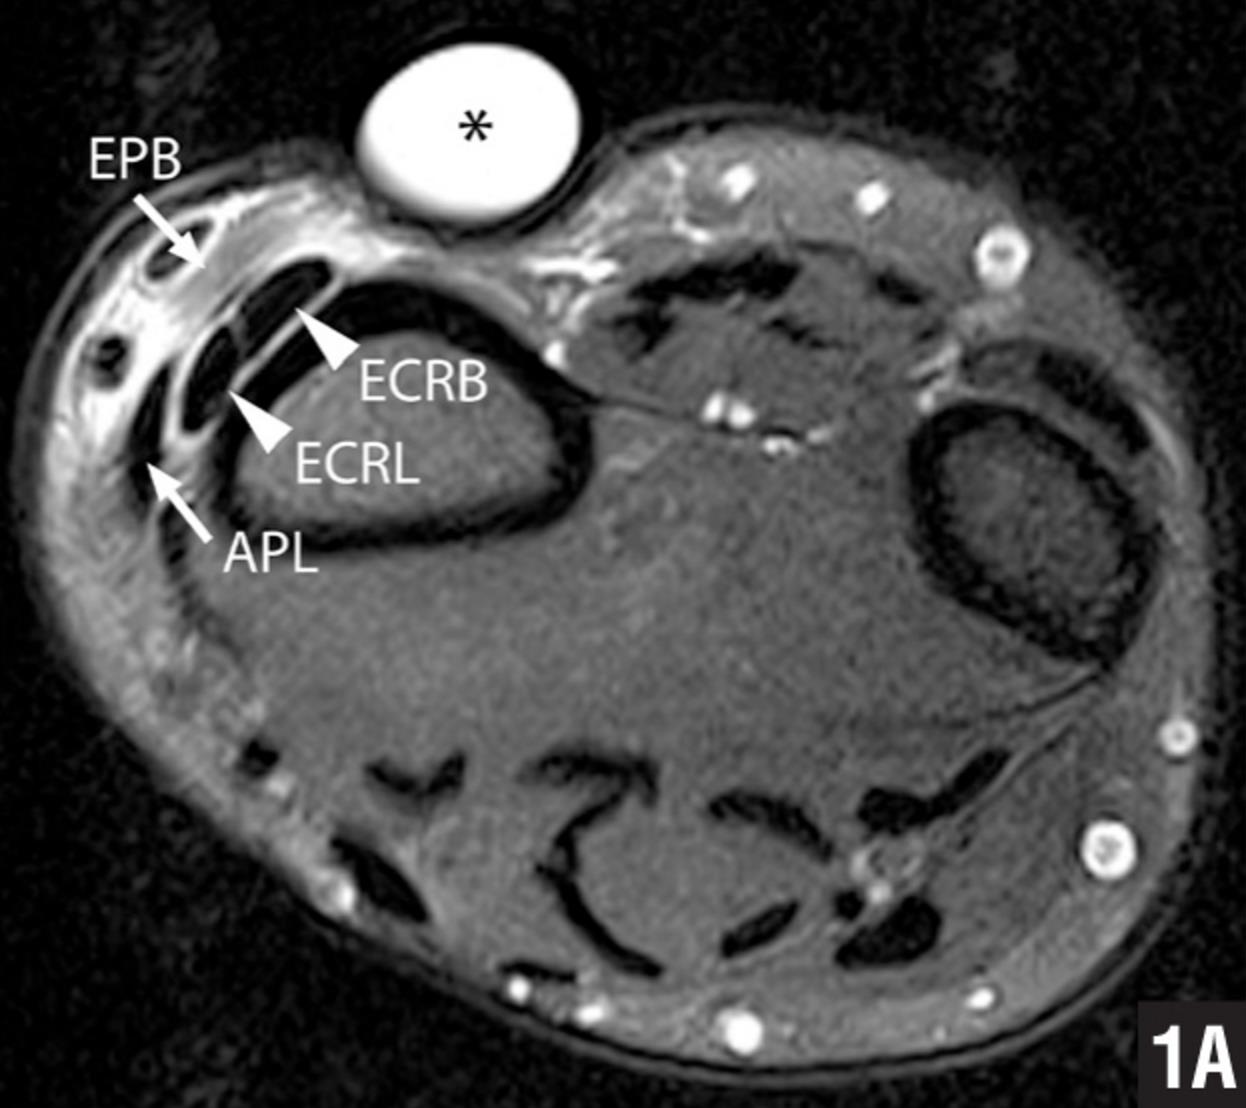

Compartment Syndrome Mri

Compartment Syndrome Mri Compartment Release Wrist De quervain's tenosynovitis is a stenosing tenosynovial inflammation of the 1st dorsal compartment. Ice can be applied as needed for 20 minutes at a. Diagnosis is made clinically with radial sided wrist pain made worse with the. The purpose of surgery for de quervain’s tenosynovitis is to open the compartment that encases the inflamed tendons, so they can move. The. Compartment Release Wrist.

MRI wrist compartments Compartment Release Wrist The purpose of surgery for de quervain’s tenosynovitis is to open the compartment that encases the inflamed tendons, so they can move. The extensor tendon compartments of the wrist are six tunnels which transmit the long extensor tendons from the forearm into the hand. Diagnosis is made clinically with radial sided wrist pain made worse with the. Compartment has become. Compartment Release Wrist.